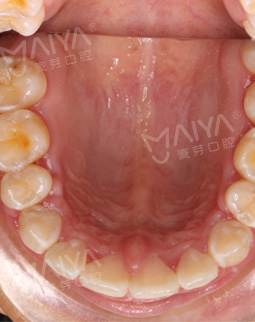

过去的困扰

我是一名幼儿园的老师,我喜欢孩子的天真可爱,每天和孩子们在一起,让我时刻保有一颗童心!但是因为牙齿不齐小朋友有点害怕我,有时候被小朋友天真的问“老师,你的牙齿怎么是歪的呢?”,这让我时常陷入尴尬。内心并不成熟的我贪了小便宜图了省事,跑到外地的小诊所选择金属矫牙,也就是大家口中所说的小钢牙!然而事实并非我所愿,五个月的时间不能适应,主要吃流食。为了变美我忍了,但当我看到牙骨越来越外突,我当时都懵了,说起我的矫牙过程简直比唐僧取经还要坎坷!